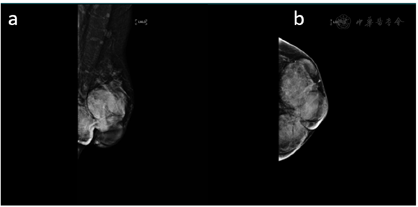

行乳腺X线摄影检查所见:左乳外份、内份及中央区分别见直径约41 mm、40 mm、31 mm的肿块影,密度增高,边缘可见透明晕圈征。左乳外份另见孤立点状钙化。左乳头稍凹陷。

乳腺X线摄影提示左乳多发肿块,建议进一步检查MRI(BI-RADS 0类)(图3)。